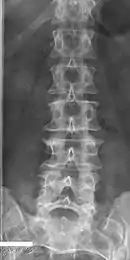

Transitional vertebrae

Short ribs at the first lumbar vertebra, which is thus a transitional vertebra, since lumbar vertebrae normally do not have ribs attached to them.

Transitional vertebrae have the characteristics of two types of vertebra. The condition usually involves the vertebral arch or transverse processes. It occurs at the cervicothoracic, thoracolumbar, or lumbosacral junction. For instance, the transverse process of the last cervical vertebra may resemble a rib. A transitional vertebra at the lumbosacral junction can cause arthritis, disk changes, or thecal sac compression. Back pain associated with lumbosacral transitional vertebrae (LSTV) is known as Bertolotti's syndrome. One study found that male German Shepherd Dogs with a lumbosacral transitional vertebra are at greater risk for cauda equina syndrome, which can cause rear limb weakness and incontinence.[10]